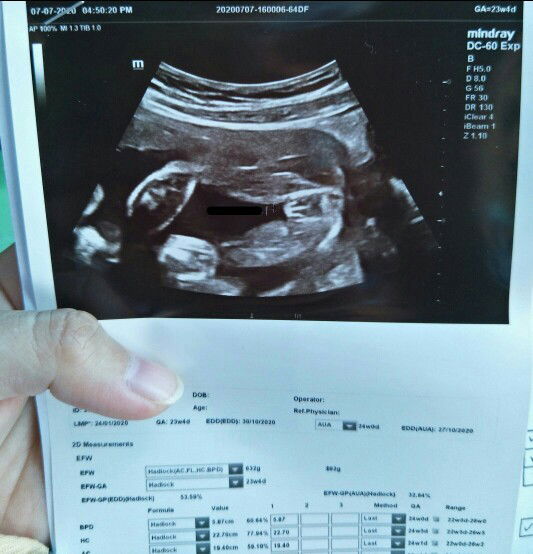

detailscan

Boy or girl? 😅

Baca lagiGirl, sbb saya masa scan doktor ckp kalau ada 3garisan maknanya girl.. Kalau boy mmg lg jelas bersuluh🤣

Burger sign.. Probability girls tu high

girl sebab ada tulang tengah

3 alur means girl